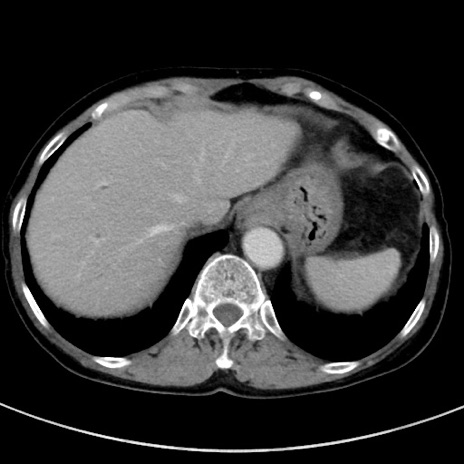

冠状断像

【症例】70歳代女性

【主訴】下腹部痛・嘔吐

【現病歴】2日前より腹痛あり。昨日嘔吐あり。症状改善しないため来院。

【既往歴】胃GISTに対して胃部分切除後。

【身体所見】BT 37.1℃、BP 128/77mmHg、腹部:平坦・軟、下腹部に圧痛あり。

【データ】WBC 10200、CRP 0.31